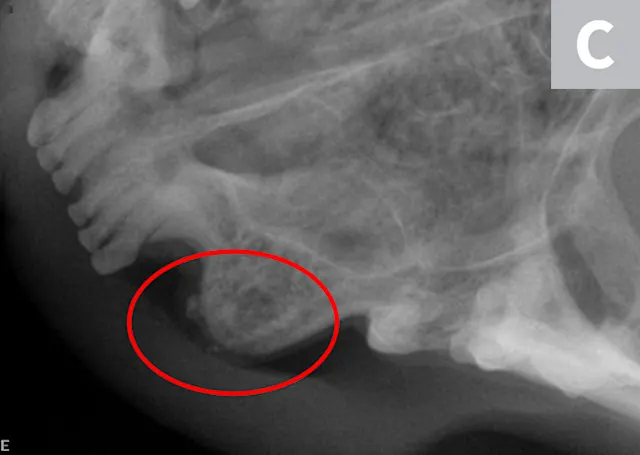

A complete oral examination and full-mouth dental radiographs were performed with the patient anesthetized. The detailed oral examination confirmed unhealed extraction sites with sharp crown fragments protruding from the alveoli into the oral cavity. In addition, an advanced TR lesion was noted affecting the left maxillary third premolar tooth (Figure 3). Dental radiographs confirmed advanced type 2 resorption affecting all involved teeth, as well as oral extension of the remaining tooth structure (Figure 4).

FIGURE 3

Intraoral radiograph of the left maxilla revealing type 2 tooth resorption on the third premolar (arrow). Extraction is indicated.